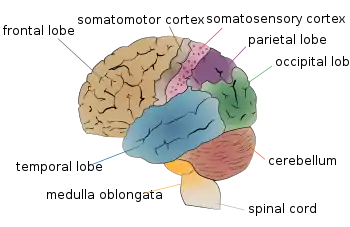

Medulla oblongata part of the brain stem (purple colored) | |

The medulla oblongata or simply medulla is a long stem-like structure which makes up the lower part of the brainstem.[1] It is anterior and partially inferior to the cerebellum. It is a cone-shaped neuronal mass responsible for autonomic (involuntary) functions, ranging from vomiting to sneezing.[2] The medulla contains the cardiac, respiratory, vomiting and vasomotor centers, and therefore deals with the autonomic functions of breathing, heart rate and blood pressure as well as the sleep–wake cycle.[2]

Lobes